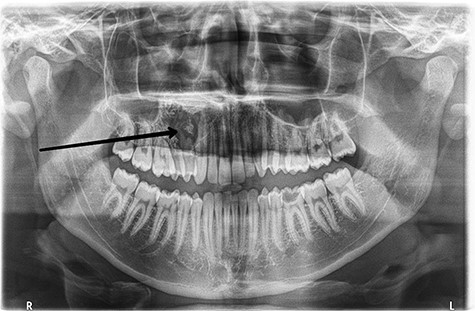

Preoperative orthopantomogram shows the radiolucent area with the calcified lesions in the right hemi-maxilla with resorption in the roots of the upper right premolars.

A 21-year-old male patient presented with swelling in the right maxilla (Fig. 1). The patient had noticed this swelling for the first time 5 months ago in the palatine process of maxilla. This swelling has grown larger within these several months and has spread from the vestibule of the mouth reaching the upper right premolars. Orthopantomography revealed a radiolucent area with calcified lesions and resorption in the roots of the mentioned premolars, reaching the root of the canine as shown in (Fig. 2). Neck ultrasound revealed normal findings. Under topical anesthesia, an oval incision was performed. Histo-pathological findings are shown in (Fig. 3). Immunohistochemistry was performed using vimentin, B-cell lymphoma (Bcl-2), p53 and Ki-67.Vimentin was positive, whereas Bcl-2 and p53 were negative; Ki-67 was expressed by 10–15% of the mesenchymal cells (Fig. 4). In view of these histo-pathological and immunohistochemistry findings, a low grade AFS was diagnosed. After that, the patient underwent a right hemi-maxillectomy with clear margins (1.5–2 cm). Vestibular and palatal mucosal flaps were eradicated. The maxillary bone split from the lateral side of the 21st tooth toward the maxillary tuberosity with complete removal of the maxillary sinus up to the orbital floor. Then, antimicrobial gauzes were applied and we left the wound healing by secondary intention (Fig. 5). A second histo-pathological study confirmed the low grade AFS. The anterior and posterior surgical bone margins were focally involved by the tumor; therefore, another surgery was performed to fully remove the tumor. Because of the deep invasion of the tumor, the surgical procedure was followed by radiotherapy. A radiographic follow-up with head and neck computerized tomography after 3 months revealed that there were no metastases to the surrounding lymph nodes. Delayed reconstruction and rehabilitation should be taken into considerations.